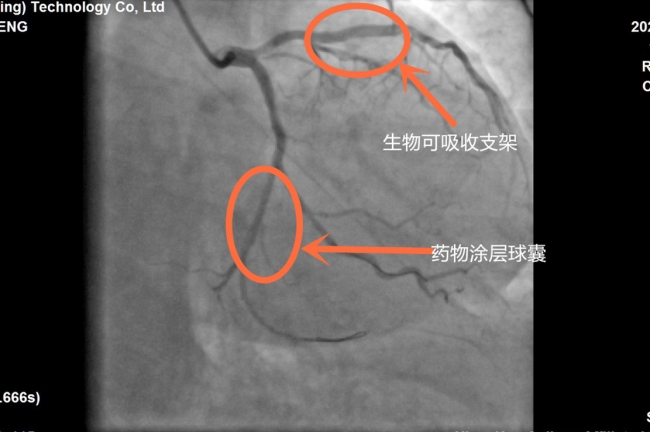

“我们常用的手术方式有置入金属药物支架和冠脉无置入技术(生物可吸收支架)两种。” 心血管内二科主任李维军说,“目前生物可吸收支架主要成分为左旋聚乳糖,完全降解时间为1年,它具有与金属支架一样强大的支撑力,相对于金属药物支架而言,生物可吸收支架由于不含金属成分,还可以有效减少发生晚期不良事件风险。”

经过患者及家属权衡利弊后,最终选择冠脉生物可吸收支架。7月5日,在医务人员的精心安排下,患者成功接受了冠脉血运重建手术。术后,胸痛症状明显缓解,段大妈高兴地说,“以前总觉在心脏里面放支架很可怕,了解到这种生物可吸收支架在植入后能够随着时间逐渐被分解吸收,我的心里踏实了很多。”